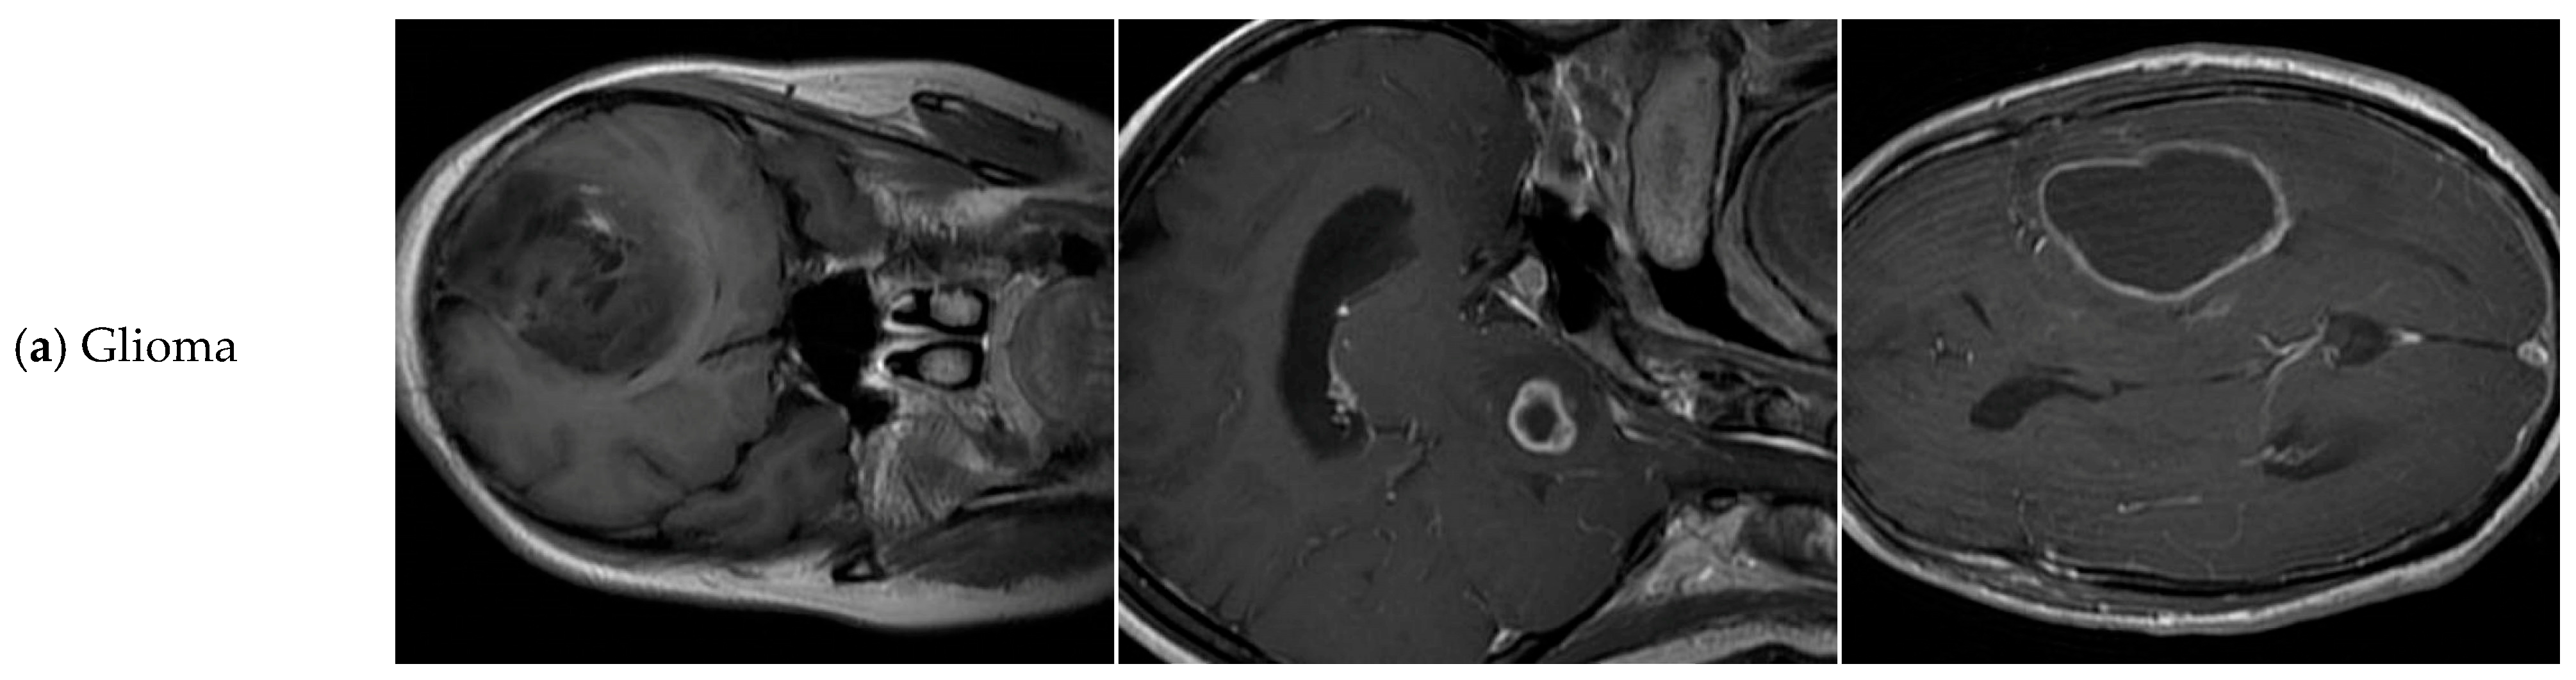

4.7. Supplementary Experiment